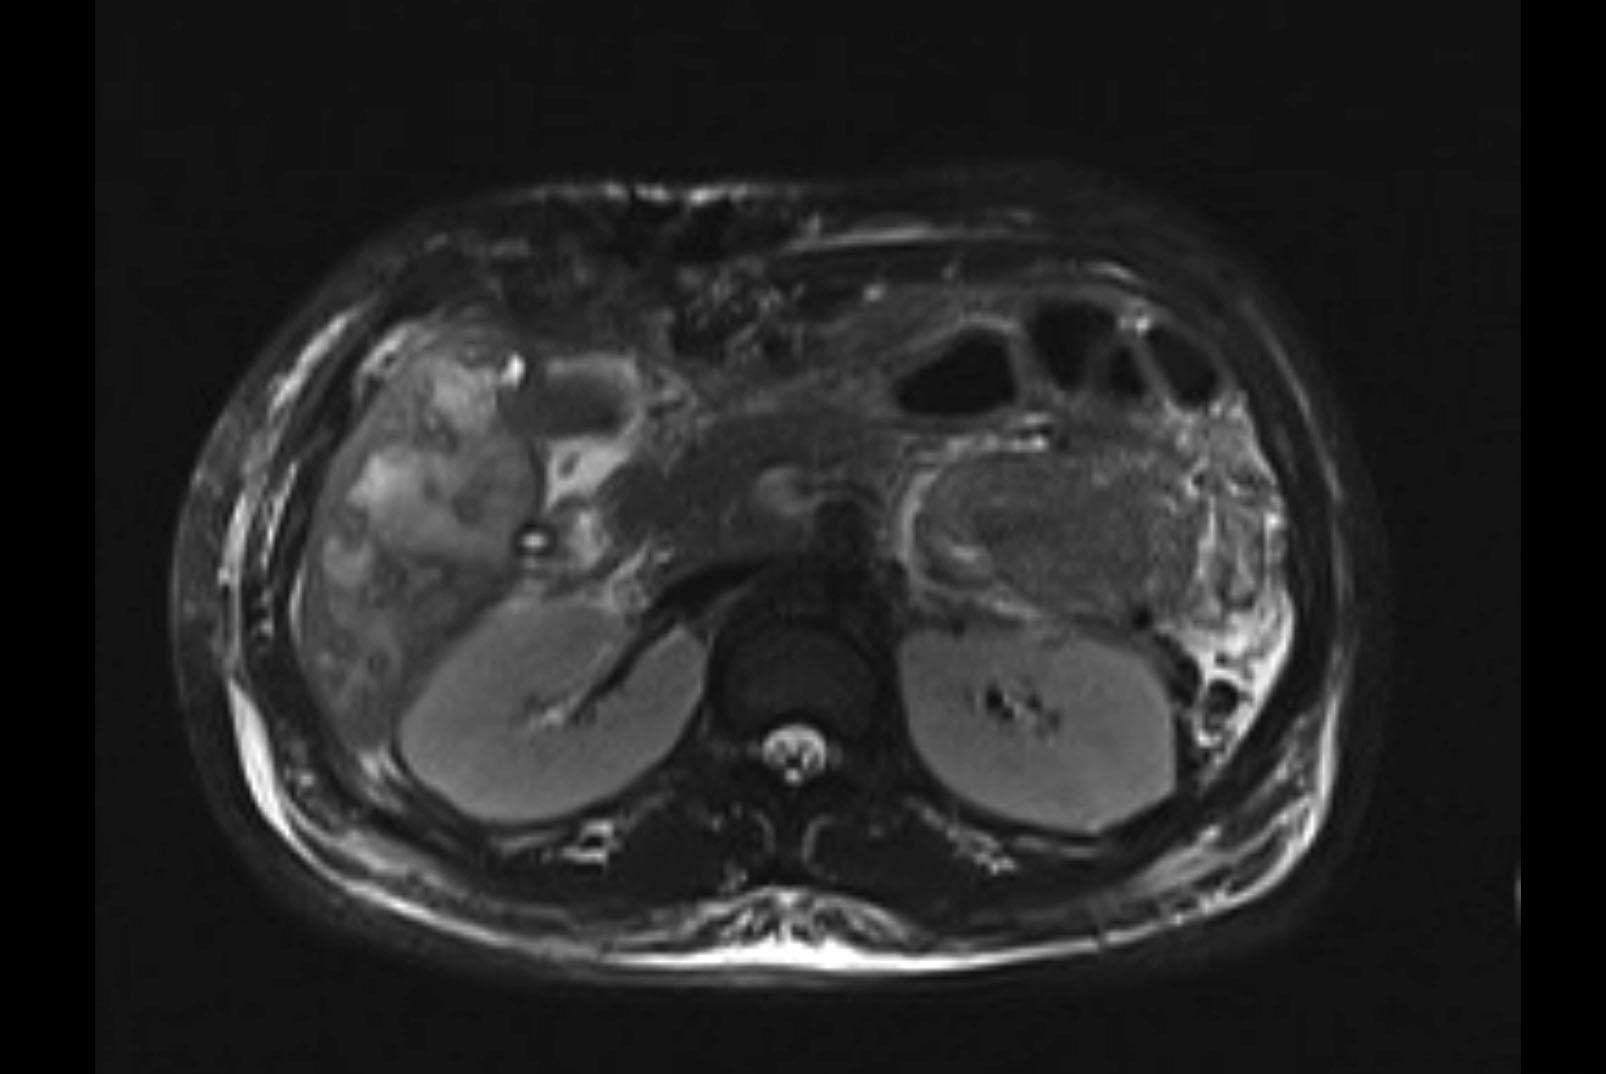

MRI T1

MRI T2

Imaging analysis

Based on initial findings, which issue(s) would you be most concerned about?